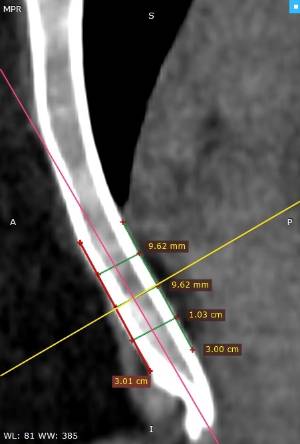

Los datos médicos del paciente, más la exploración clínica realizada por el equipo de cirugía, junto a un análisis pormenorizado de las imágenes del TAC y las reconstrucciones digitales en 3D de cada tórax realizadas conjuntamente con el equipo de ingenieros de Ventura Medical Technologies, son la base para determinar si la técnica Pectus Up está indicada y como se debe proceder en cada uno de los pacientes.

Con estos datos se selecciona el implante que mejor se ajustar a la anatomía de cada tórax, la ubicación exacta del sistema de elevación y, a su vez, proporciona al equipo quirúrgico un detalle de los pasos a tener en cuenta para llevar a cabo una correcta implantación.

Informe de evaluación del TAC de un paciente enviada al cirujano